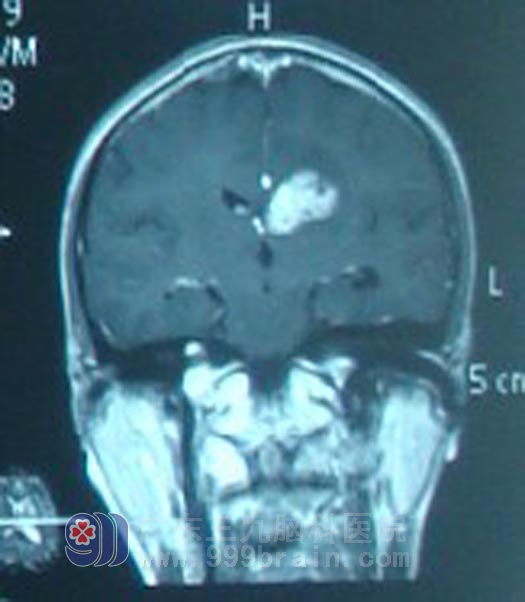

28岁的阿军一直都是一个快乐、很容易和人“混熟”的男孩。可是5年前,阿军无明显诱因出现头痛头晕伴恶心呕吐等症状,食欲差,短短2月,消瘦明显,在当地检查后以慢性乙肝保肝治疗,肝功好转但症状无明显改善,阿军还是常常会出现上述症状,且还逐渐出现了多饮多尿症状。原本开朗随和的小伙子也变得脾气暴躁,在这些症状持续半年后,阿军在一次头颅CT检查中被诊断为颅内多发占位性病变。http://www.999brain.com/

为求进一步治疗,当即赶到广东三九脑科医院就求医。入院后,医生结合影像及症状、血清肿瘤标记物等检查综合考虑为生殖细胞瘤可能性大。在征得阿军及其家属同意后,予以诊断性放疗。放疗10Gy后复查显示阿军的肿瘤明显缩小。遂进一步确诊为生殖细胞瘤。继续予头颅放疗及全脊髓预防照射。放疗后阿军一直遵医嘱定时化疗及复查,5年来未见肿瘤复发征象。前日阿军女朋友陪阿军来复查,影像未见肿瘤复发,生活状态如正常人。

治疗前